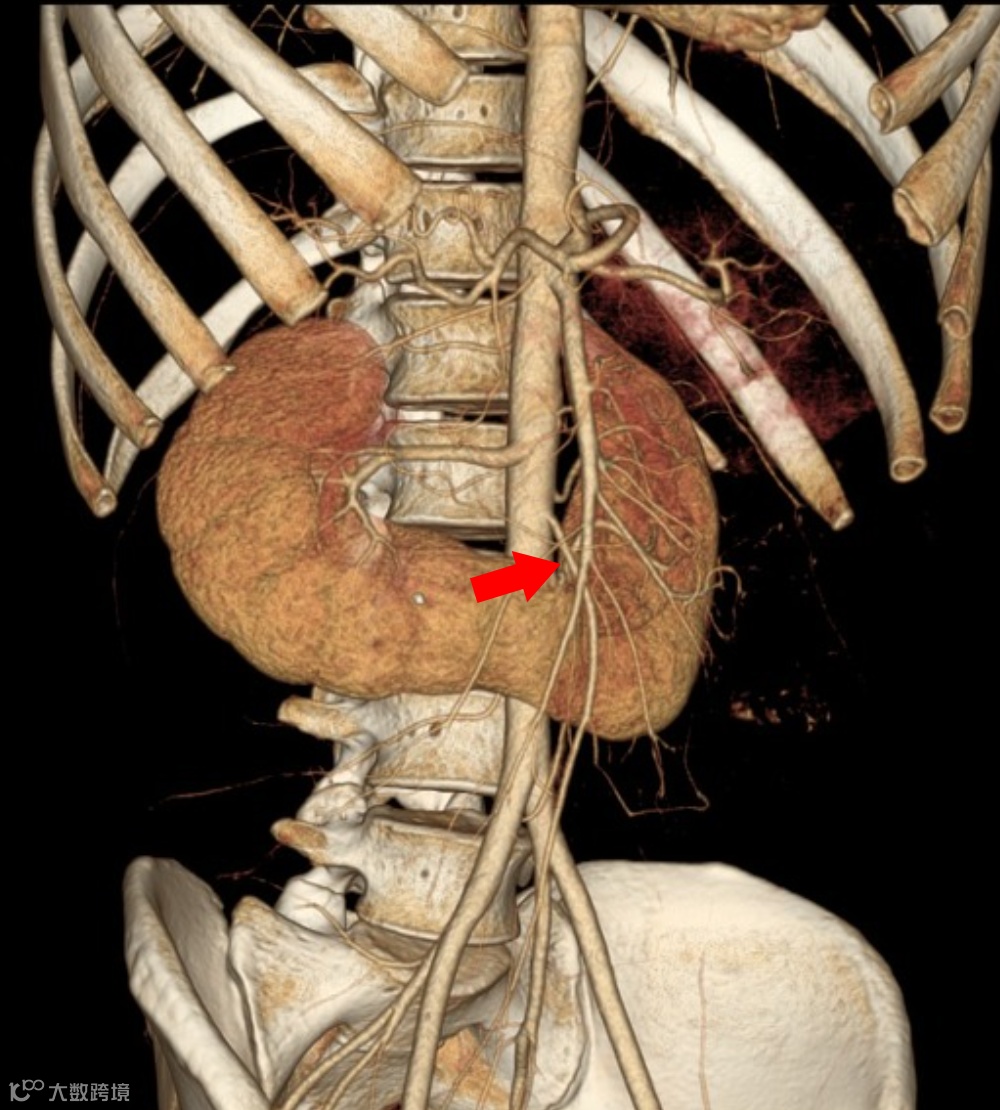

马蹄肾,双肾下极融合,峡部位于肠系膜下动脉(箭头)起始水平的下方。

患者,男,60岁,因怀疑主动脉夹层而进行CTA检查,发现马蹄肾,肾峡部可见功能性肾实质,由三条肾动脉供血(箭头)。